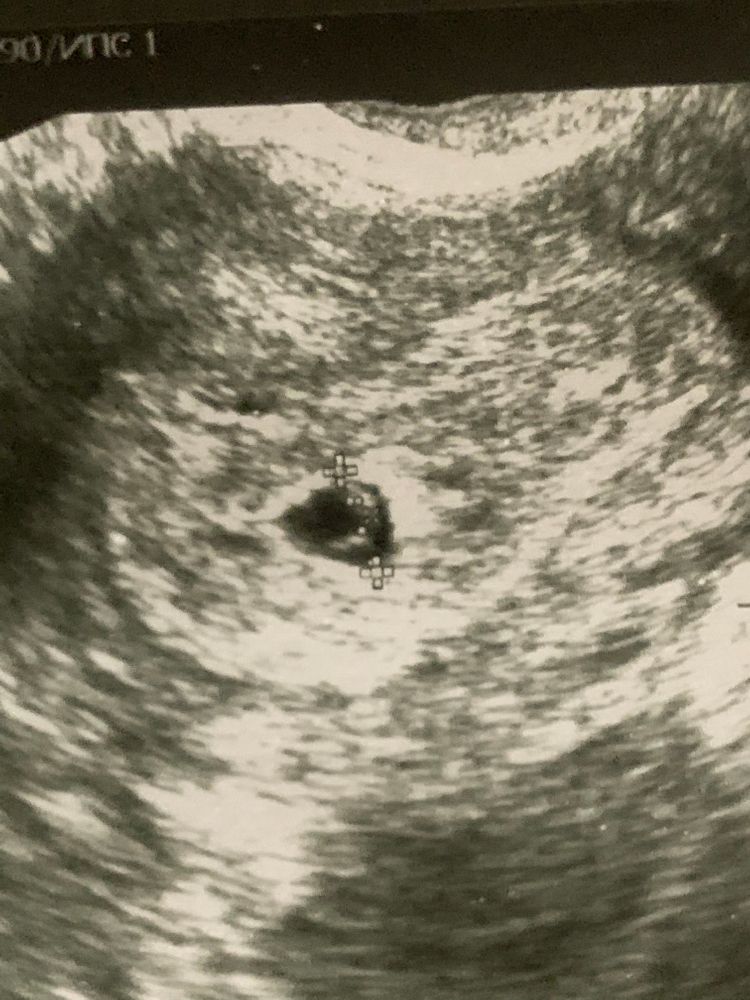

ПЯ 7,6мм. КТР 3,2мм. ЗБ ? 😔

Анна, т.к 32 дпо , и вычитала что разница между ктр и пя должно быть минимум 5мм.

Жанет , а у вас 4,5. Может быть погрешность УЗИ. Поздняя овуляция! Подождать неделю и переделать УЗИ

Наиса , 9 дней назад пя-3,6 было. Выросло всего на 4 мм…